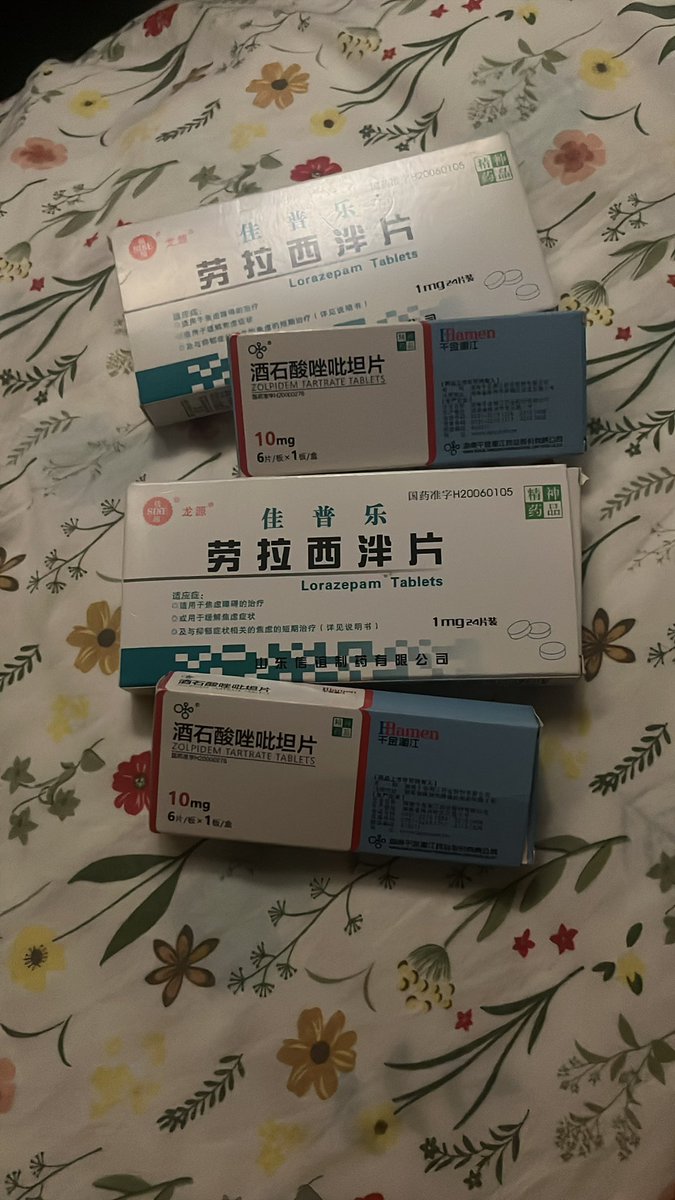

对于药物过量引起的中枢神经系统副作用,有一些不常见或常见的药物来控制症状。

罗通定:拮抗多巴胺

赛庚啶:血清素综合症

异丙嗪:在低剂量下没有抗精神病作用,和其他所有抗组胺药一样可以缓解过敏。止吐

喹硫平:不清楚是什么引起的症状就干脆谁都别玩了吧()似乎很万能的急救

评论区欢迎补充 https://t.co/7S4tGVDEM5

牧雨 @_mucha_000@AnIncandescence bzd

炽烈已极 @AnIncandescence@_mucha_000 bzd太多了而且大家好像都知道可以用?我看看有没有特别侧重某些效果的bzd

炽烈已极 @AnIncandescence苯二氮卓类药物:镇静作用。bzd通过提高内源性化学物质GABA的有效性来降低神经元的兴奋性。 https://t.co/Z1mc5JJGrg

炽烈已极 @AnIncandescence已知阿普唑仑对伴有恶心呕吐症状的过量有额外作用,它本身有联用其他药物治疗化疗引起的恶心的用途。

炽烈已极 @AnIncandescence纳洛酮:可用于阿片类药物过量(可获取的上市药品)需舌下给药,因肝脏首过代谢口服时利用度很低;效果持续30-90min;亦可用于酒精中毒的促醒等,但谨慎使用。

氟马西尼:苯二氮卓类药物拮抗剂,解毒剂,包括对z类药物有效;似乎没有上市药品

炽烈已极 @AnIncandescence阿托品:抗胆碱能药物(副交感神经阻断药),类似的还有东莨菪碱,苯海拉明,吩噻嗪类抗精神病药等。

可用于反制胆碱能药物过量(如多奈哌齐,石杉碱甲)